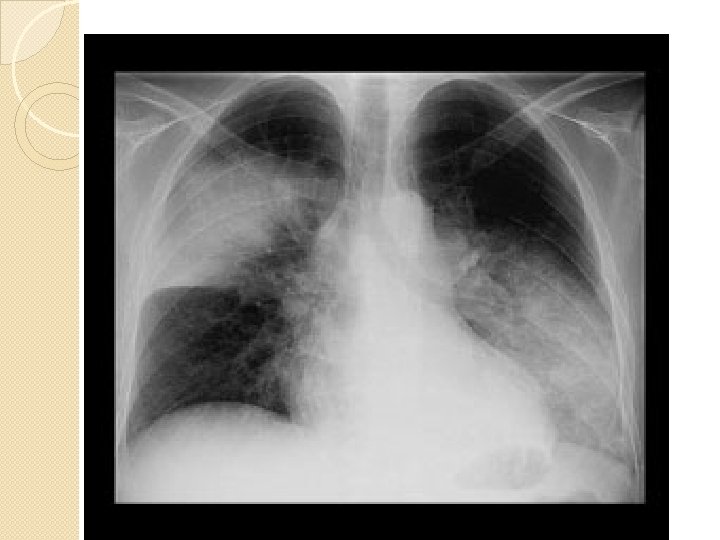

Pseudomonas aeruginosa Aspect radiologic -afectare de obicei bilaterală -predilecţie pentru lobii inferiori -caracter difuz -necroză extensivă cu formare de multiple abcese

Pneumonia stafilococica - distribuţie bilaterală - abcese cu perete subţire - pleurezie bilaterală - pungă pleurală stg.